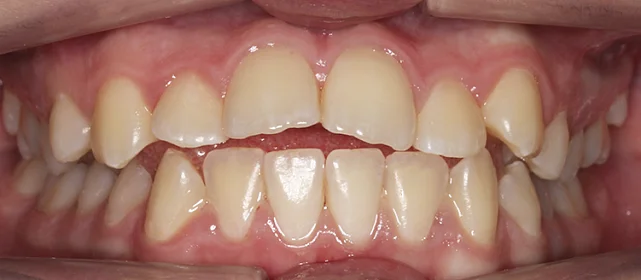

Зубы выровнены, смыкание нормализовано. Установлены несъёмные ретейнеры на обе челюсти, сняты сканы для ретенционных кап.

Решение: Поставили прозрачные элайнеры Click — начали с компактного набора из 20 кап. Основной комплект сделал основной объем работы, но для финальной доводки понадобился дополнительный набор из 10 кап. Итого 30 кап за 23 месяца. Результат — зубы на месте, смыкание в норме. Зафиксировали ретейнеры на обе челюсти, сняли сканы для ретенционных кап.

Небольшой по объёму случай — 20 кап в основном наборе. Этого хватило для основного выравнивания, но финальная коррекция смыкания потребовала ещё 10 кап. Предпочитаю доработать, чем оставить компромиссный результат. 30 кап за 23 месяца — спокойный темп, без спешки.